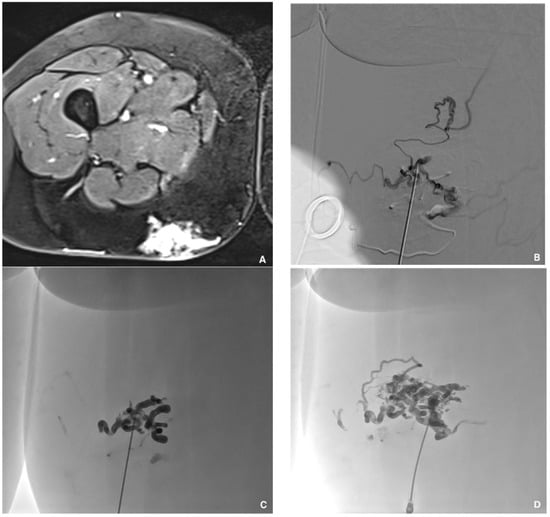

Figure 5. Superficial painful buttock arteriovenous malformation (AVM) in a 61-year-old patient. (A) Axial magnetic resonance imaging shows posterior subcutaneous contrast enhancement at the arterial phase, corresponding to the AVM. (B) Direct puncture of the nidus with a 21-gauge metallic needle and opacification of the nidus. (C) Embolization with a Glubran®2/Lipiodol® mixture of a 1:5 ratio. (D) Final result after complete embolization of the nidus.